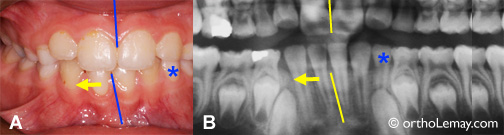

Dans d’autres cas, comme celui illustré ci-dessus, il peut y avoir asymétrie dans la position des incisives sans qu’une canine ne soit tombée.

(A, B) Les incisives se sont déplacées vers la droite (flèche) de la ligne médiane (pointillé jaune) et une latérale inférieure (*orange) est bloquée et ne peut sortir par manque d’espace .

Il serait alors indiqué d’extraire la canine non du côté où il manque d’espace (droite du patient) mais du côté opposé (gauche) (* bleu = canines temporaires, losange rouge = canine à extraire). Extraire la canine droite ne ferait qu’augmenter la tendance qu’ont les incisives à migrer vers la droite en leur donnant plus d’espace.

Après un délai de ± 12 mois, l’autre canine (* bleu 2) pourra être extraite. Il est possible qu’après un tel délai la position des incisives se soit améliorée un peu sans aucune autre intervention.